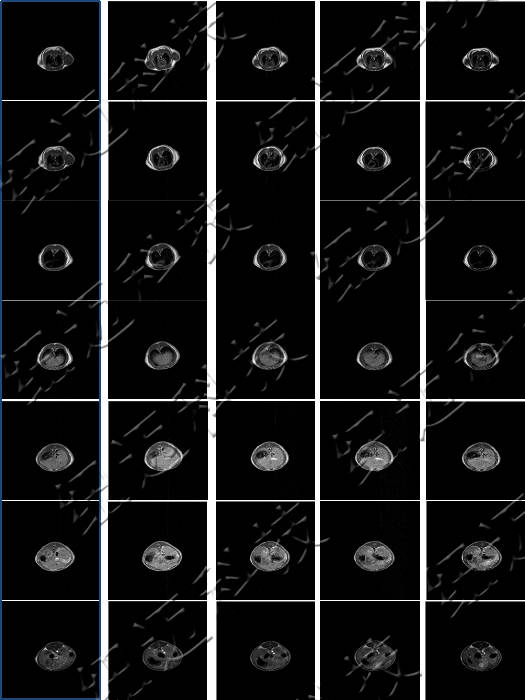

测试钆类MRI造影剂弛豫率测试以及造影剂样品的T1加权成像。

核磁共振成像(MRI)目前普遍应用于医学检测成像中,具有无辐射损伤的安全性,可任意方位断层扫描等技术灵活性,加以涵盖质子密度、弛豫、加权成像以及多参数特征的优势,已成为当代临床诊断中最有力的检测手段之一,然而临床发现某些不同组织或肿瘤组织的弛豫时间相互重叠,导致诊断困难。

核磁共振成像因其具有无创、快速、高解析率、高对比度等特点,在临床上广为使用。特别是在肿瘤的诊断中,该技术利用病变组织和正常组织物理特性的不同而获得的结构、功能影像,已经成为原发肿瘤和肿瘤转移早期诊断中不可或缺的重要依据。